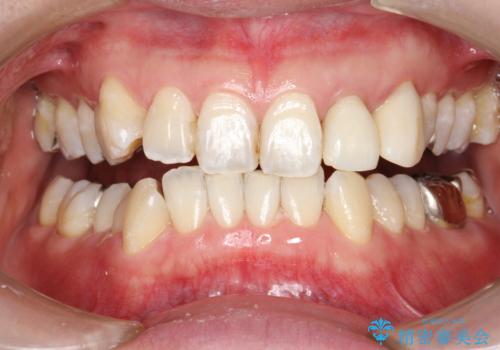

- 半年ぶりの来院で、全体的なチェックとクリーニング希望でした。PMTC(自費クリーニング)60分コースを行いました。

PMTCとは、プロフェッショナル(歯科衛生士)メカニカル(機械的)トゥース(歯)クリーニング(清掃)の略です。歯科医院にて、いろいろな機械・材料を使用し汚れを落とします。

磨き残しや、細菌は歯の表面がザラザラしている部分につきやすいです。そのためPMTCを定期的に繰り返すことで、歯の表面がツルツルの状態である期間が長くなるため、虫歯や歯周病予防につながります。